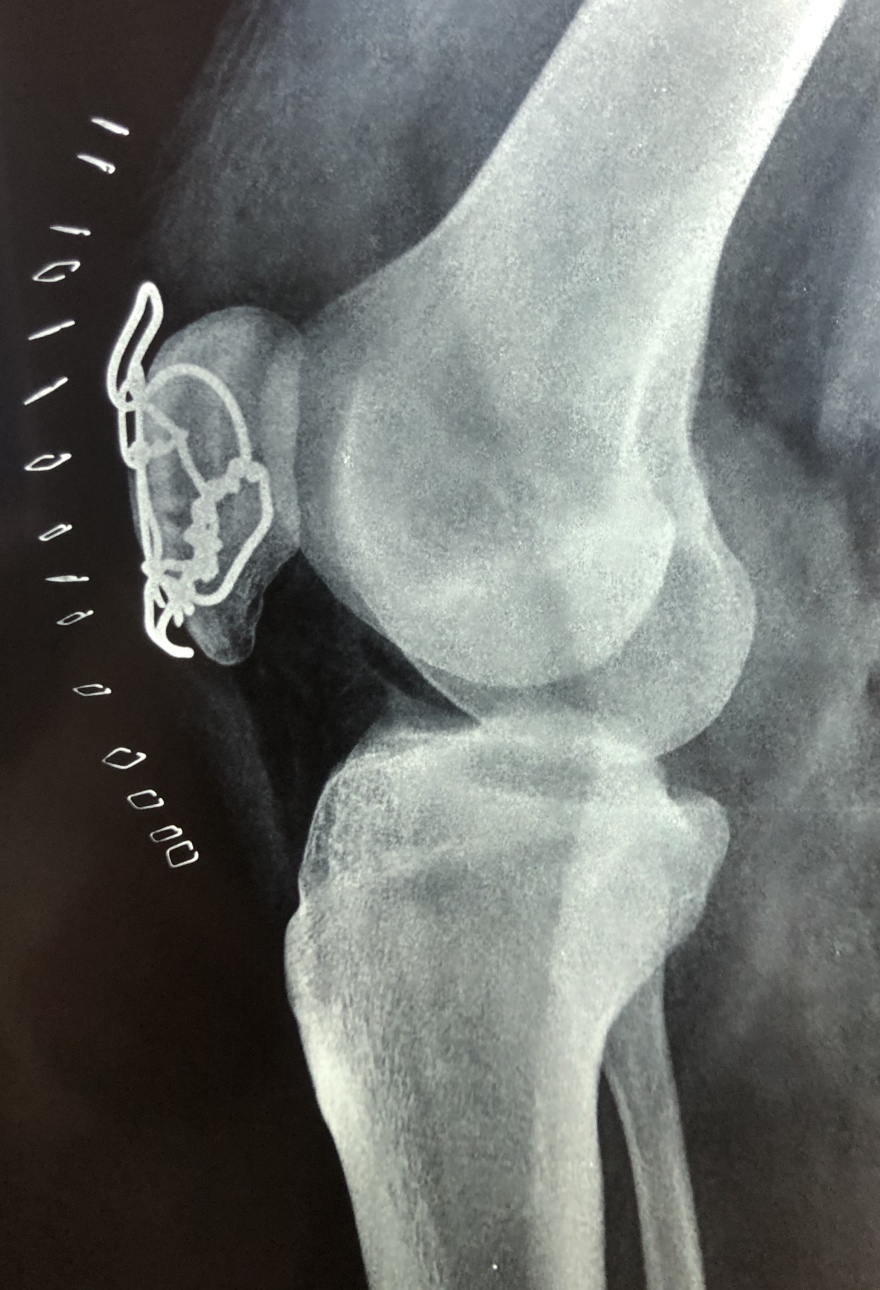

Δείτε ακτινογραφίες πριν την επέμβαση:

Τζάνειο νοσοκομείο: Νέα μέθοδος για την αντιμετώπιση συντριπτικών καταγμάτων της επιγονατίδας